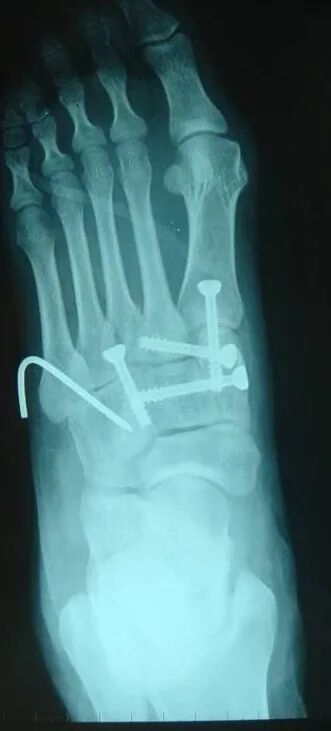

内固定选择1、克氏针:优点是手术简单、时间短、对周围组织损伤小,缺点是固定不坚强、复位丢失等情况时有发生。2、可吸收螺钉:优点是不需行二次手术取出内固定物,缺点是固定强度不及传统螺钉3、小螺钉系统:经典 --- 3.0mm、3.5mm、4.0mm4、空心螺钉:3.0mm、4.0mm、4.3mm 、4.5mm5、微型钢板:跨关节固定,对于严重的跖骨粉碎性骨折的患者,螺钉无法固定时,建议选择微型钢板桥接固定6、骑缝钉

根据三柱理论1、首先复位内侧柱并临时固定 2、再复位固定中间柱3、如外侧柱移位可能需双切口

手术从第一跖骨和内侧楔骨开始。首先直视下复位该关节,评价楔骨之间的稳定性,关节囊通常撕裂,但仍然需要掀开以充分显露关节,清除关节内的软组织和软骨碎片。

内侧柱稳定后,开始处理第二跖骨和中间楔骨。点式复位钳由第二跖骨基底部外侧远端斜向内侧楔骨内侧面的近端夹持,注意避免第二跖骨向下移位,发生复位不良。

若楔间关节仍不稳,可使用楔骨间螺钉;固定内侧两跖骨后,通常第三跖骨已经足够稳定,若仍未复位,可以参考第一跖骨固定方法固定。通过第二切口固定第4、5跖骨。可以使用克氏针固定。

Lisfranc损伤骨折复位标准:1、C形臂透视显示正、侧、斜位均为正常解剖复位2、如复位后第1、2跖骨基底间隙和内、中楔骨间隙<2mm,跖跗骨轴线<15°为近解剖复位,可以接受,超过这个范围的移位则无法接受3、复位好后,沿第一跖骨轴线向内侧楔骨逆行拧入一枚4.0mm皮质骨螺钉。螺钉由关节远侧1.5-2.0cm处进入,平行于足底或略向跖侧。

4、从内侧楔骨向第二跖骨置入一枚螺钉,重建韧带。螺钉自内侧楔骨近端的背侧置入,指向第二跖骨背侧皮质的下方,螺钉应通过4层皮质,确保对第二跖骨的双皮质固定